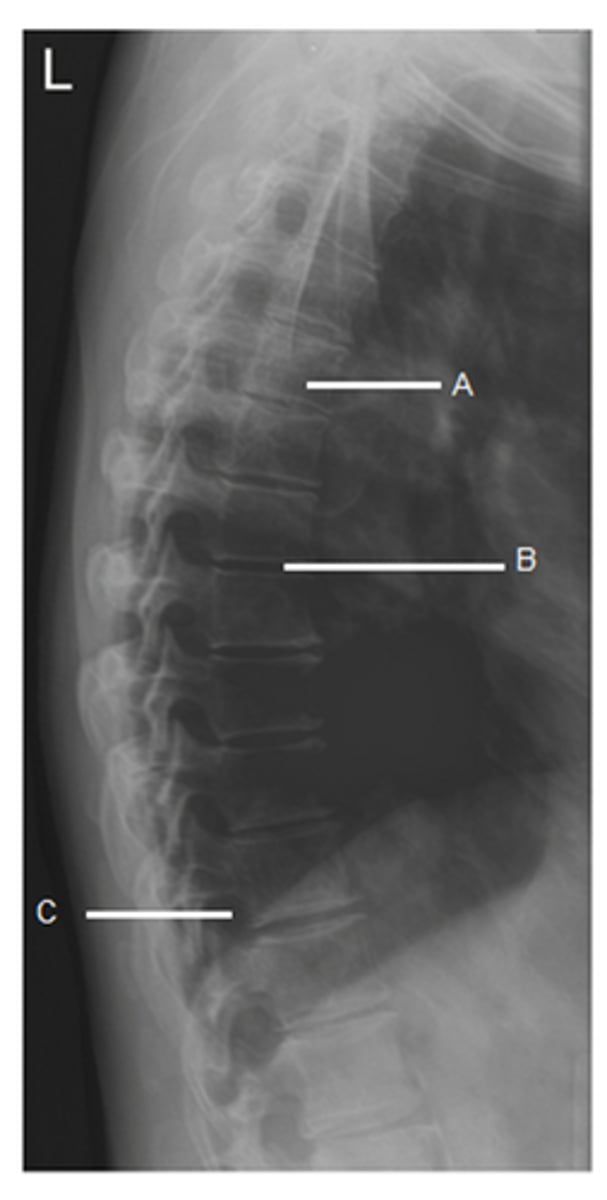

What does 'B' represent?

intervertebral disk

In the image, 'B' represents:

Zygapopgyseal joint